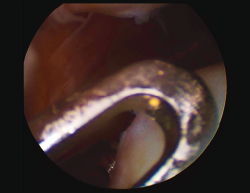

First surgery involves arthroscopy of the damaged joint. It assesses the chondral lesion to be treated and confirms whether it is amenable to the chondrocyte implantation technique (Figures 1 and 2). Other procedures are also carried out if needed, such as for example reconstruction of the anterior cruciate ligament, partial meniscectomies, meniscus implantation, patellar realignments, osteotomies, etc. Lastly, the cartilage sample is taken from a non-weight bearing zone (intercondylar zone or internal femoral condyle at its upper margin). The sample is extracted with biopsy forceps or, alternatively, using discectomy forceps. Between 3-4 rice grain-sized fragments of healthy cartilage are harvested (Figure 3). The biopsy material is placed in a sterile receptacle containing a culture medium (DMEN) (Figure 4). The material is kept at room temperature and is shipped to the laboratory as quickly as possible. A form should be completed (Figure 5), stating the joint, the location of the lesion and the size of the defect. Once in the laboratory, the sample is processed and cultured. After 4-6 weeks (depending on the case), the culture is ready for implantation.

Figure 3. View showing biopsy of the cartilage of the internal femoral condyle, internal and upper margin.